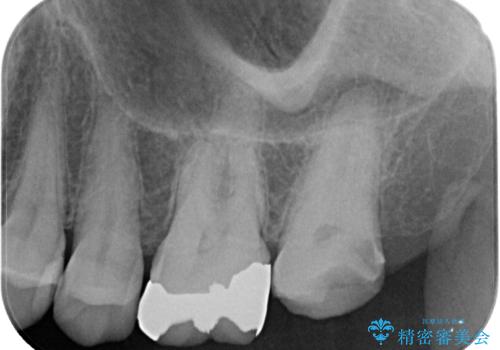

- 上の奥歯を放置してしまったとのことで来院された患者様です。

虫歯が大きいのでクラウンによる治療が必要となりますが、咬む力がとても強いために、歯と同じ堅さであるPGAクラウン(白金加金合金クラウン)をお勧めしました。

上の奥歯であることから、審美性よりも機能性を優先され、ゴールドクラウンを選択されました。